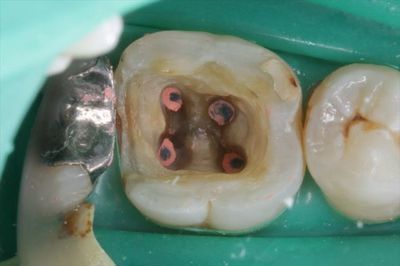

4根管性の右下第一大臼歯です。(顕微鏡(マイクロスコープ)ミラー像)